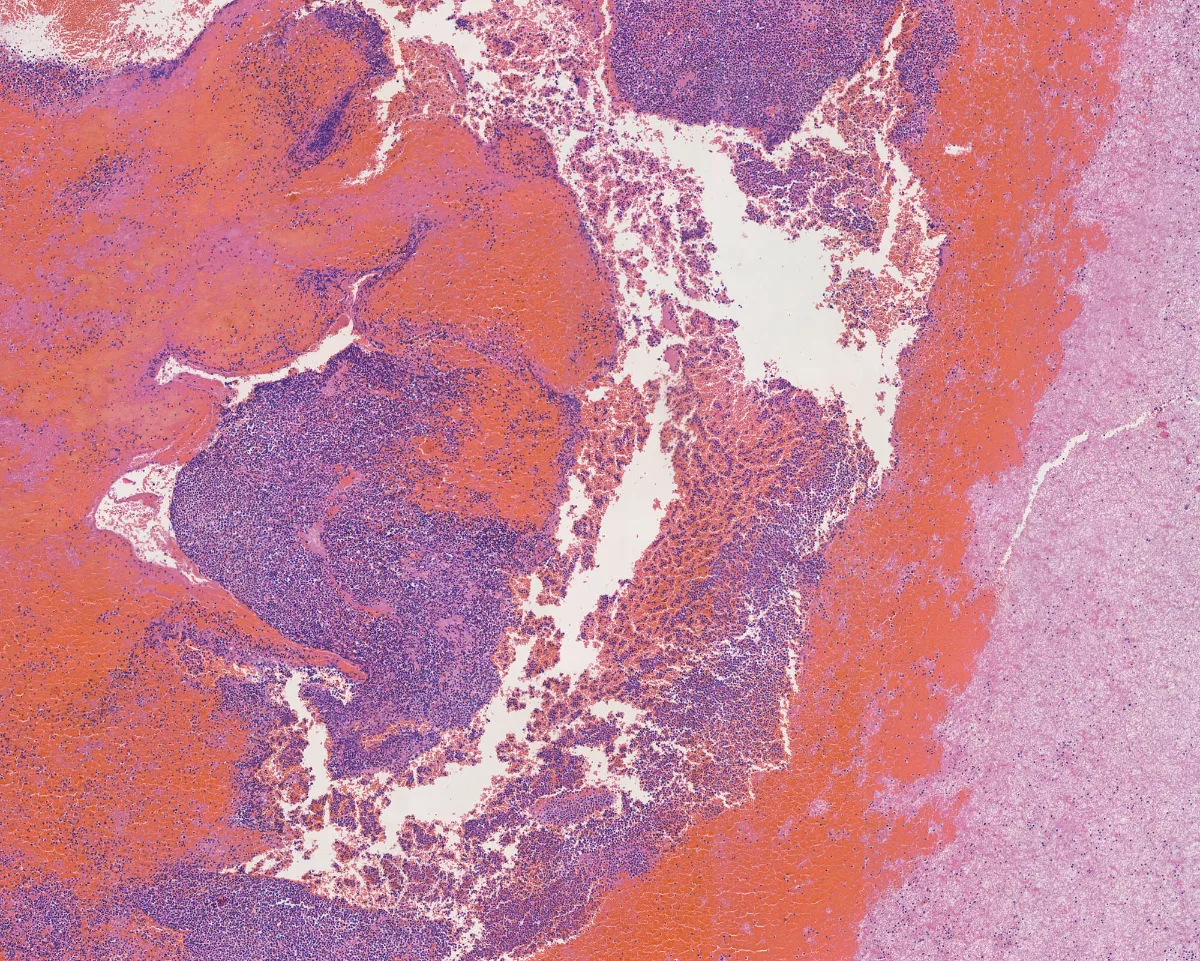

Imágenes:

Hematoxilina-eosina 1

- Está compuesto por sábanas de células de tamaño intermedio de origen mieloide, positivas para CD34 y MPO (PMID: 39328673).